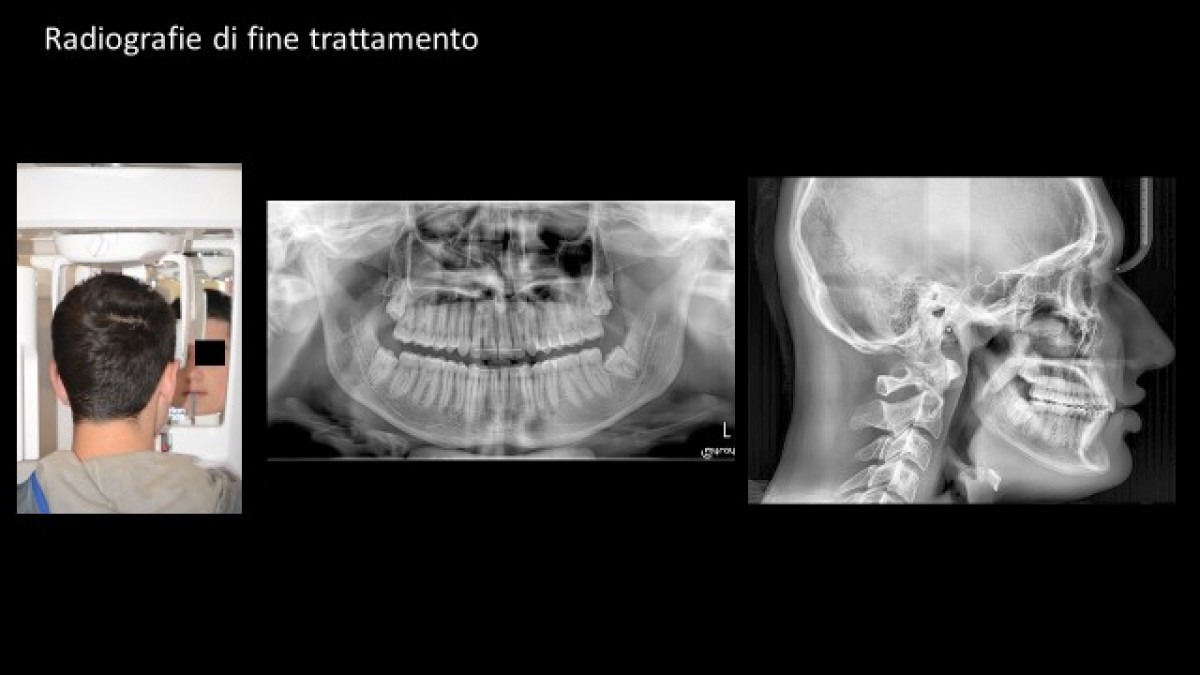

The panoramic X-ray performed with the Hyperion (MyRay) equipment highlighted the good condition of the teeth and mandibular condyles and showed the presence of the molar buds (fig. 3).

The lateral and frontal teleradiography images (MyRay Hyperion), allowed us to clearly identify all the anatomical structures - skeleton, teeth and soft tissues - essential for the execution of correct cephalometric analysis, which constitutes the cornerstone of the diagnosis and treatment plan (fig. 4).

Final cephalometric analysis and treatment start-end image overlap show that, in this case at least, the personalised braces were effective in correctly positioning and angling the upper and lower incisors (fig. 16).